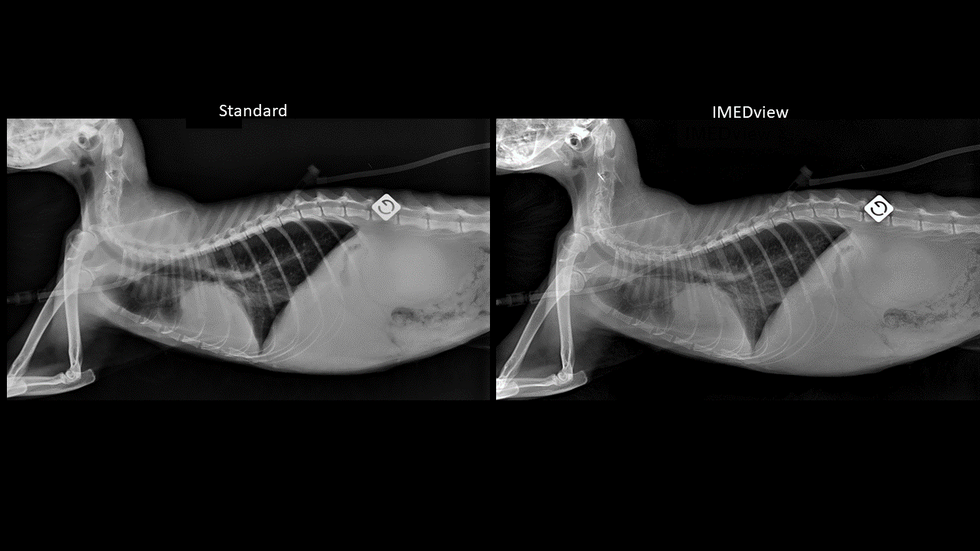

Radiographies avec un post-traitement Standard vs IMEDview